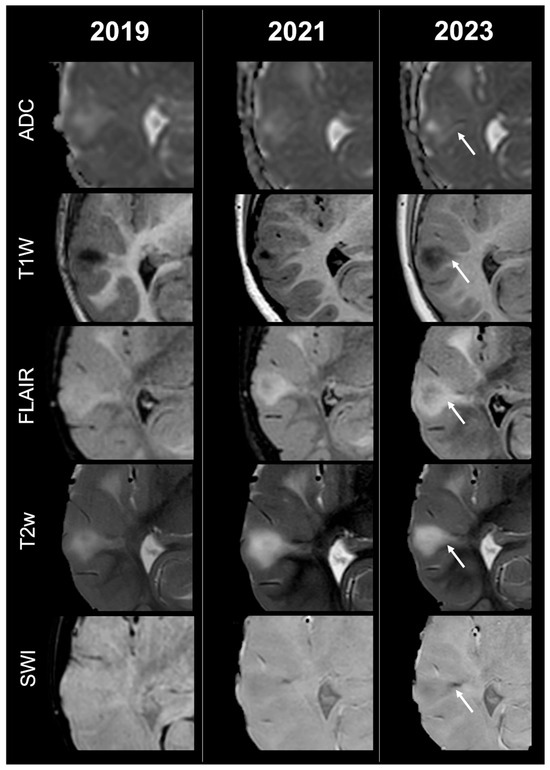

Concerning total lesion count, the interobserver agreement was excellent, with an ICC of 0.91 (95% CI: 0.87–0.95). At baseline, the total number of CTs identified across the cohort was 918 (mean ± SD = 16.1 ± 12.4), whereas at the last available MRI follow-up, the overall count increased to 1070 (mean ± SD = 18.8 ± 13.3), corresponding to a net gain of 152 CTs, equal to a relative variation of +17%. When stratified by tuber type, distinct trajectories were observed over time. Type A CTs, which were relatively abundant at diagnosis (N = 303, mean ± SD = 5.3 ± 7.0), decreased to 255 (mean ± SD = 4.5 ± 5.9) at follow-up, yielding a reduction of 48 lesions (−16%). Conversely, type B CTs showed an opposite trend, increasing from 438 (mean ± SD = 7.7 ± 8.4) at baseline to 556 (mean ± SD = 9.8 ± 8.6) at follow-up, corresponding to a net increase of 118 tubers (+27%). An example of MRI signal evolution from tuber A to tuber B is shown in Figure 1. Similarly, type C1 CTs rose from 160 (mean ± SD = 2.8 ± 4.8) to 220 (mean ± SD = 3.9 ± 5.8), with a net gain of 60 tubers (+38%). Type C2 CTs, initially rare at diagnosis (N = 14, mean ± SD = 0.2 ± 0.8), markedly expanded to 33 (mean ± SD = 0.6 ± 1.5), accounting for an increase of 19 CTs (+136%). Finally, type D CTs were only sporadically encountered, with a modest increase from 3 (mean ± SD = 0.1 ± 0.3) to 6 (mean ± SD = 0.1 ± 0.4), equating to a 100% variation. The observed increment of type C2 tubers was attributable almost exclusively to the progressive transformation of pre-existing type B lesions and, more prominently, type C1 lesions, while the increase in type C1 tubers reflected the gradual conversion of both type A and type B CTs that were already detectable at disease onset. An example of MRI signal evolution from tuber B to C1 is shown in Figure 2, while from tuber C1 to C2 in Figure 3. Only in one patient was a type C1 tuber newly identified at follow-up without clear evidence at baseline. In contrast, newly apparent tubers emerging over time but not clearly visible on baseline scans were most frequently represented by type A and type B lesions. Type D tubers were rare overall and were identified in only six lesions from four patients with a particularly high lesion burden; in all but one case they represented the evolution of type A or type B CTs (an example of MRI signal evolution from tuber A to tuber D is shown in Figure 4), while in a single case they were associated with adjacent subtle calcific foci. Overall descriptive data are summarized in Table 1.

Figure 3.

Left occipital tuber transition from type C1 to C2 at three different timepoints in a female patient diagnosed with TSC1.